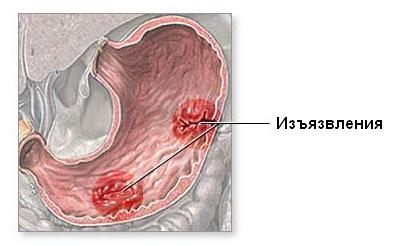

Поражение желудочно-кишечного тракта и печени

Больных беспокоят тошнота, рвота, отсутствие аппетита. Поражение пищевода проявляется его дилатацией, эрозивными изменениями слизистой оболочки. Нередко обнаруживаются изъязвления слизистой оболочки желудка и двенадцатиперстной кишки. Поражение сосудов брыжейки приводит к сильным болям в животе, преимущественно вокруг пупка (абдоминальный криз), ригидности мышц брюшного пресса.